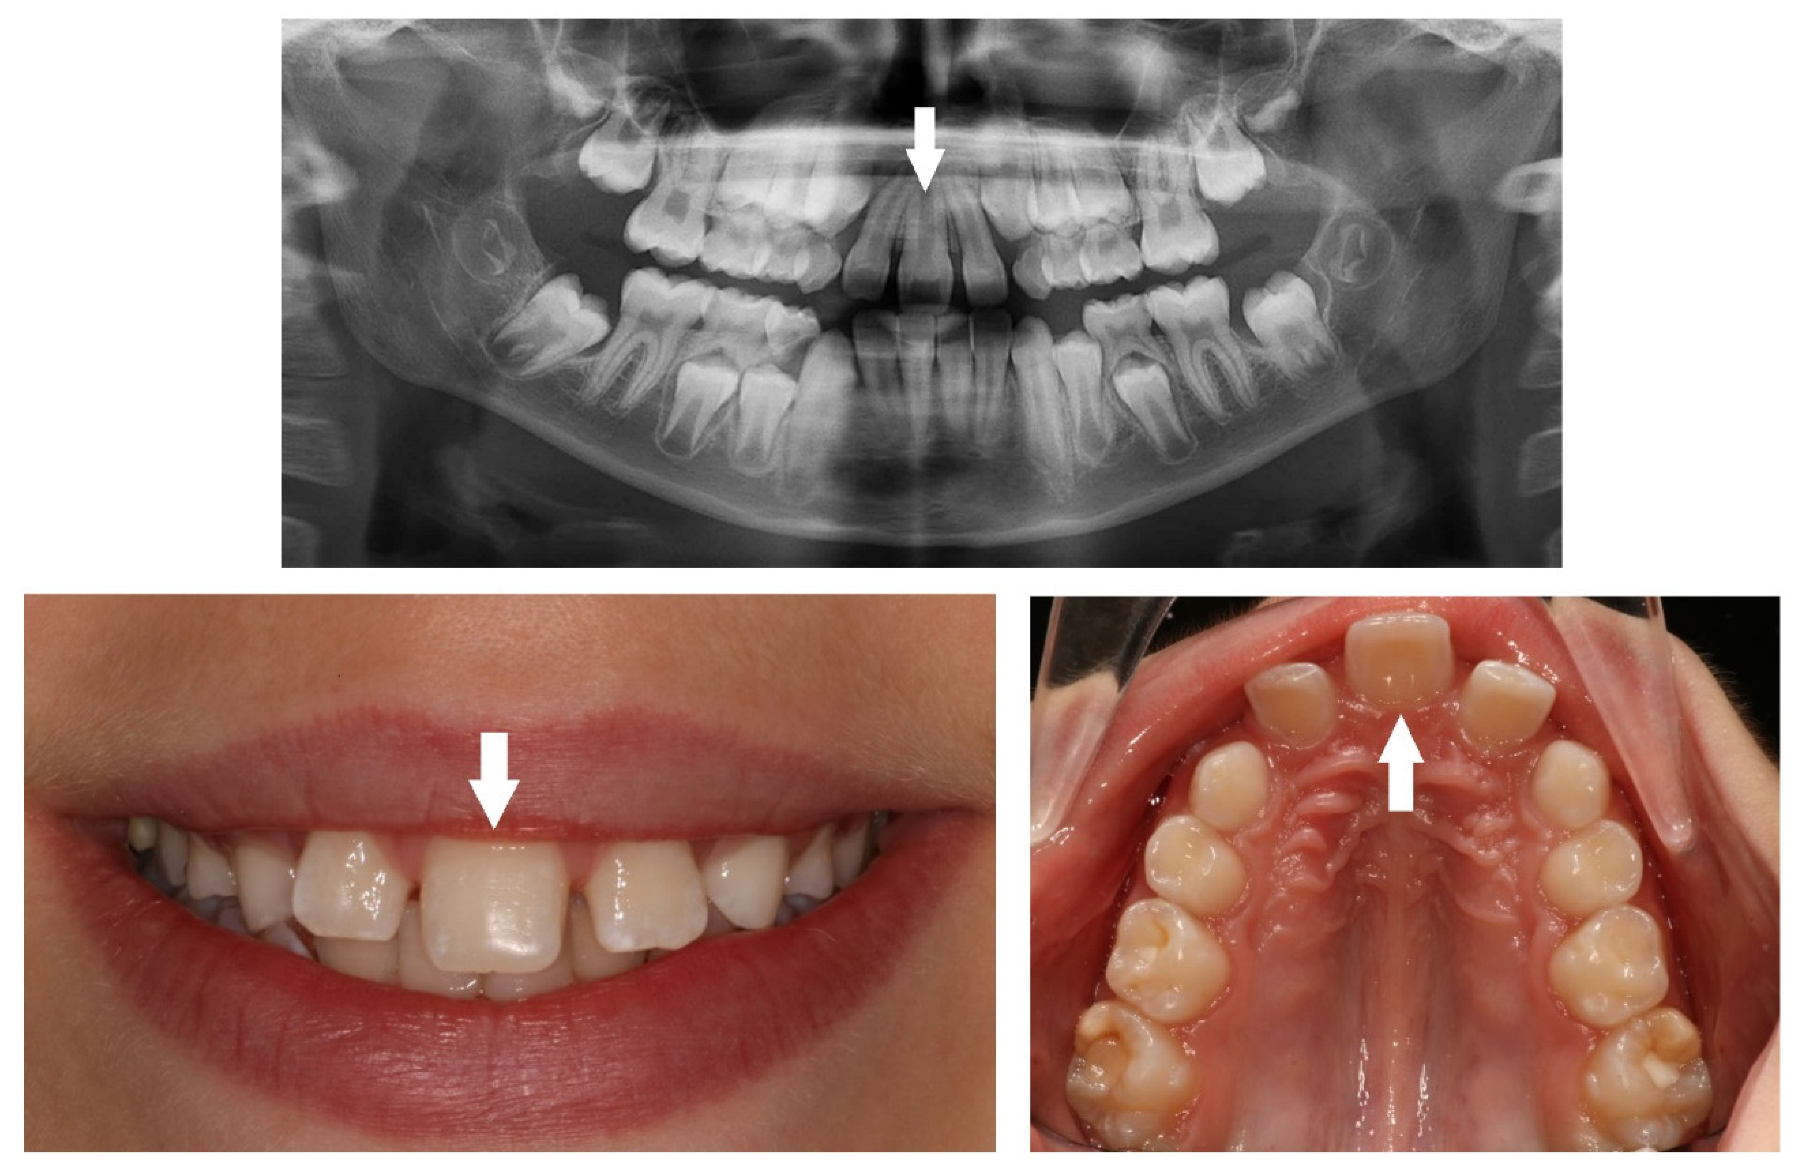

| Dental Anomaly | Diagnostic Criteria |

|---|---|

| Supernumerary | Presence of extra teeth more than the full complement of teeth. |

| Missing | Congenital absence of permanent teeth. |

| Peg-shaped | Small conical tooth with a narrowing in diameter from the cervix to the in-cisal edge. |

| Impaction | Failure of tooth eruption into the oral cavity. |

| Transposition | Two adjacent permanent teeth that switched their position within the same quadrant of the dental arch. |

| Ectopic | Eruption of teeth not in their normal position. |

| Submergence | A primary tooth positioned under the occlusal surface of the adjacent teeth. |

| Retained | A primary tooth that fails to exfoliate at the appropriate time. |